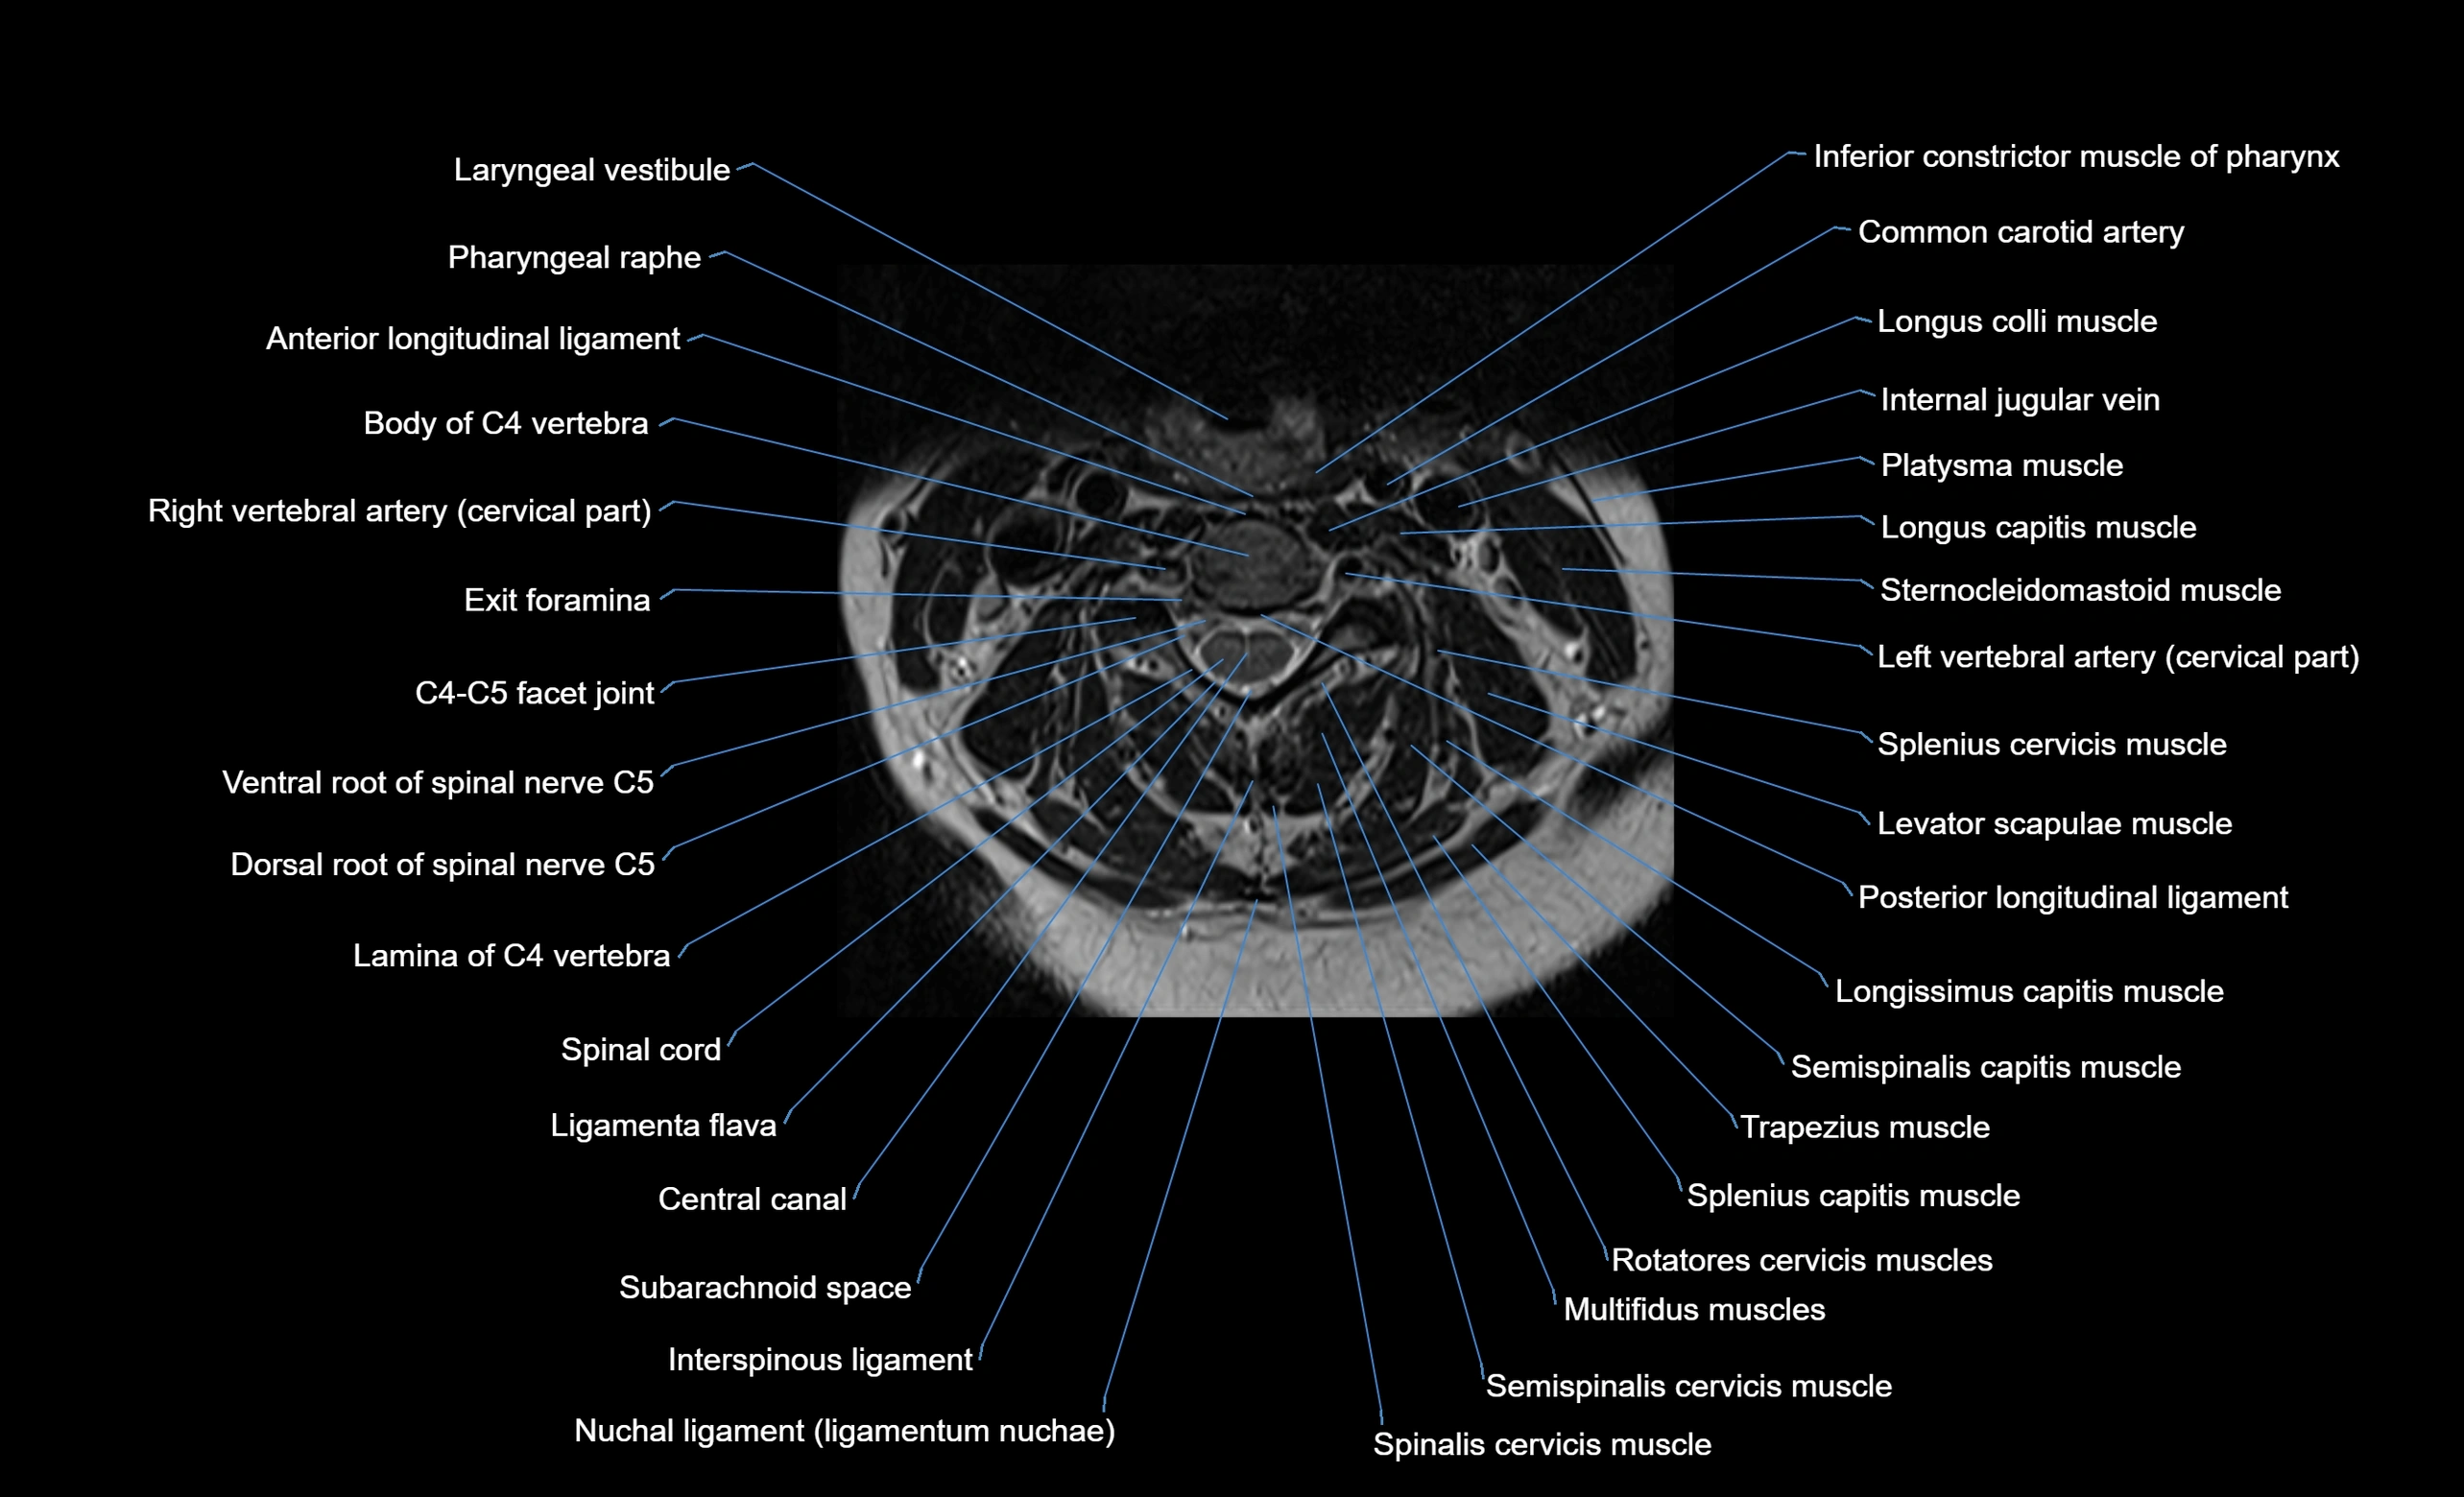

MRI image

image